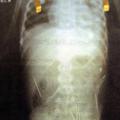

preboden Na dečku izvajal črno magijo Očim je dveletnemu dečku v telo zabodel okoli 40 igel med obredom črne magije.